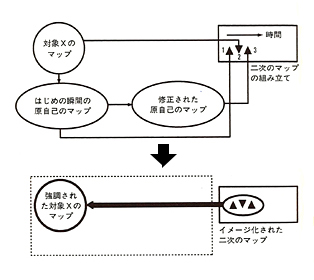

Amazon.co.jp: 生存する脳 心と脳と身体の神秘 アントニオR.ダマシオ 現代の唯脳主義を根底から揺すぶり脳と意識と自己を知る究極の本 情動と感情 : おもちゃ, 生存する脳』(アントニオ・R・ダマシオ,田中 三彦)|講談社BOOK倶楽部,

生存する脳』(アントニオ・R・ダマシオ,田中 三彦)|講談社BOOK倶楽部, ダマシオ教授の 教養としての「意識」 機械が到達できない最後の人間性 | アントニオ・ダマシオ, 千葉敏生 |本 | 通販 | Amazon,

ダマシオ教授の 教養としての「意識」 機械が到達できない最後の人間性 | アントニオ・ダマシオ, 千葉敏生 |本 | 通販 | Amazon, 1305夜 『無意識の脳・自己意識の脳』 アントニオ・ダマシオ − 松岡正剛の千夜千冊,

1305夜 『無意識の脳・自己意識の脳』 アントニオ・ダマシオ − 松岡正剛の千夜千冊, 脳を見える化